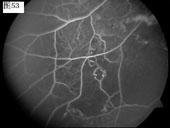

优秀眼底图片奖应征作品展示